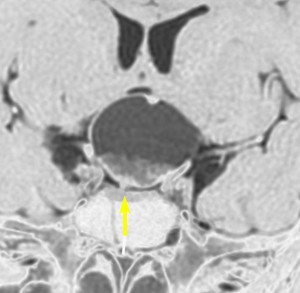

この子の症状は頭痛だけ。両親はなぜ気づかなかったのかと疑問を持ちますが,巨大になるまで症状が出ないこともあるのです。左のCTで腫瘍の周囲にバラバラと白い点状の石灰化があるので診断できます。左の視床下部から発生したクラニオでした。開頭手術しますが超高難易度です,怖いです (┯_┯) 複数回開頭手術になりましたが結果的に全摘出できています (by Dr 山本哲哉)。